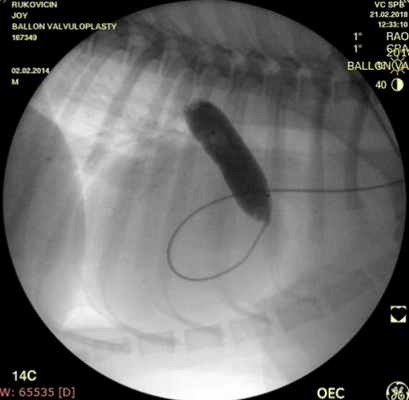

Проведено: баллонная вальвулопластика клапана легочной артерии (Тип А). Баллон Cordis maxi 40х20 мм. Инфляция до 5 атм. 10 попыток.

ЭхоКГ (после операции): ГД (градиент давления) на ЛА (легочной артерии) - 39 мм.рт.ст. РКЛА (регургитация клапана легочной артерии) – ср. - 16 мм рт.ст. Геометрия сердца не нарушена. Выраженное снижение градиента давления после баллонной дилатации КЛА (клапана легочной артерии) на 55%.